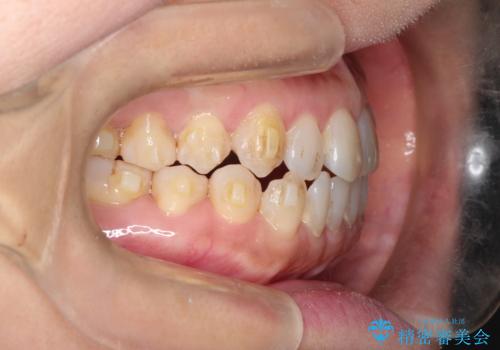

前歯の隙間 インビザラインによる目立たない成人矯正

- 前歯の隙間を気にされて来院されました。

インビザラインにて、目立たずに矯正治療を行うこととしました。

歯と歯の間にある隙間を閉じるのは、インビザラインでもしっかり治療できます。